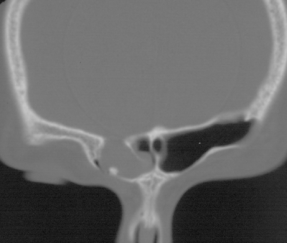

fracture du canal optique gauche avec rhinorrhée droite du fait de l’asymétrie de la cloison du sinus sphénoïdal - étage postérieur : correspondant à la face postérieure du rocher, il est en rapport avec l’oreille moyenne et les cellules mastoïdiennes, ces dernières ont la particularité de ne pas avoir de muqueuse.